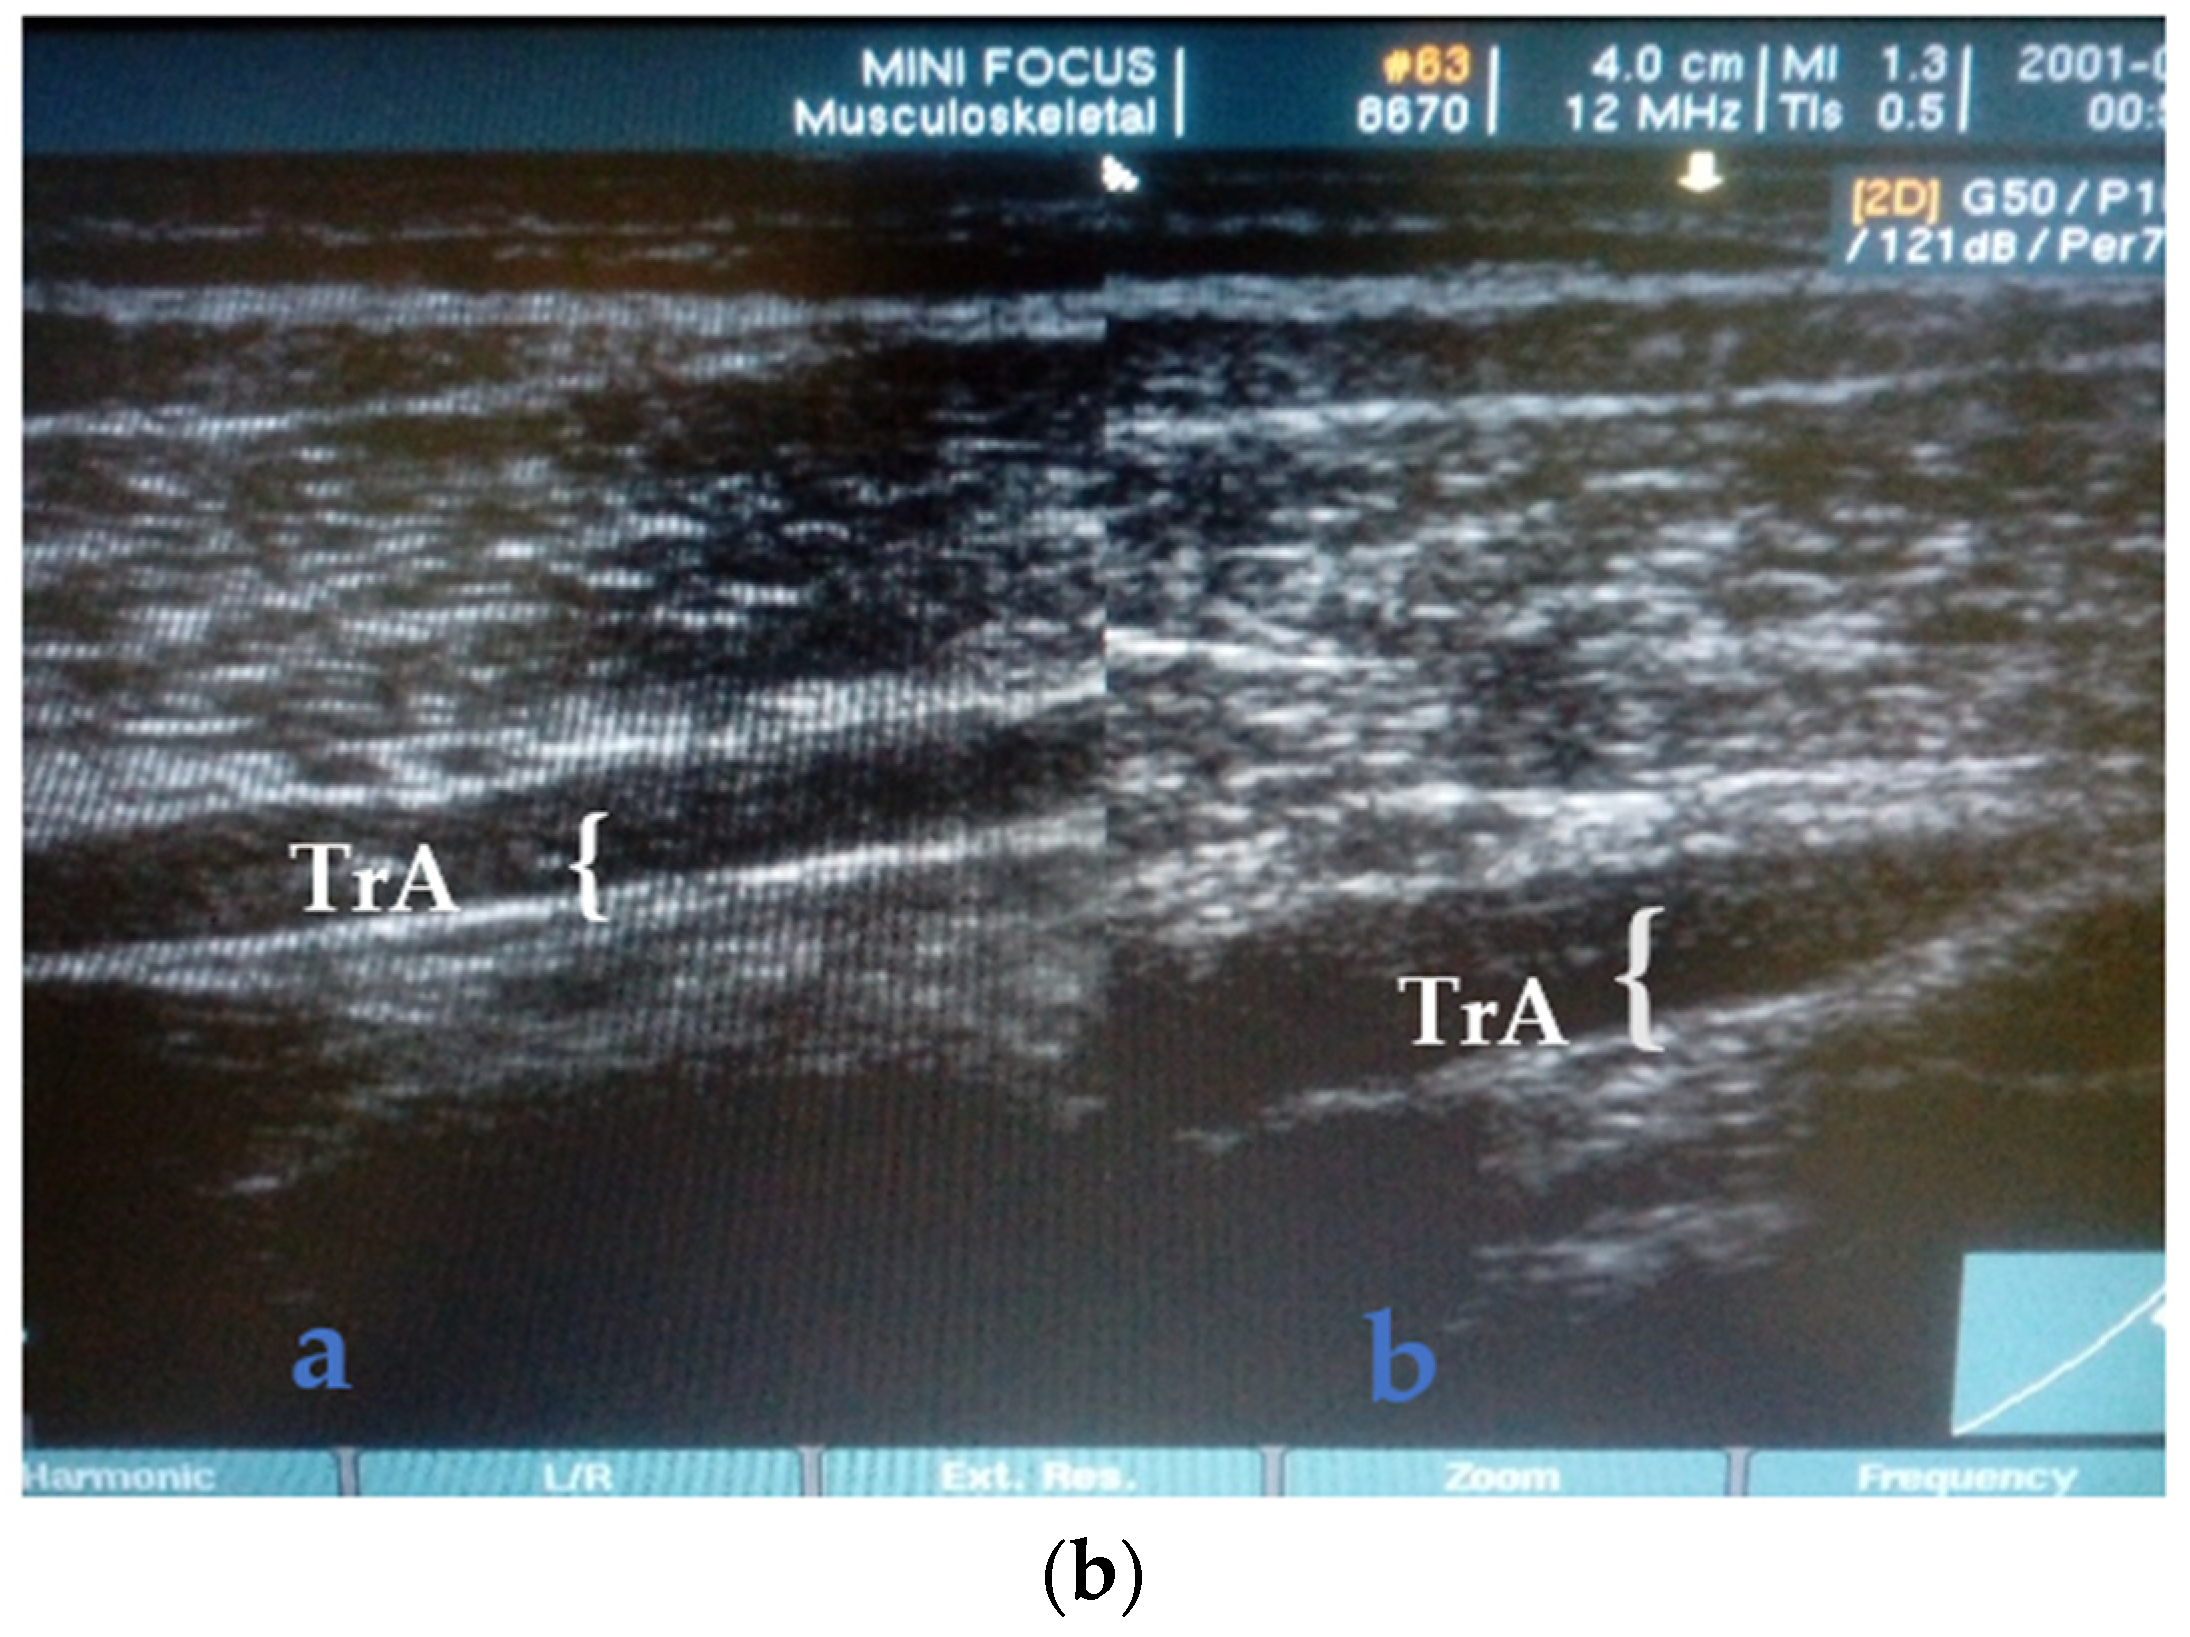

TrA Activation and Standardization of Exercise Progression Level